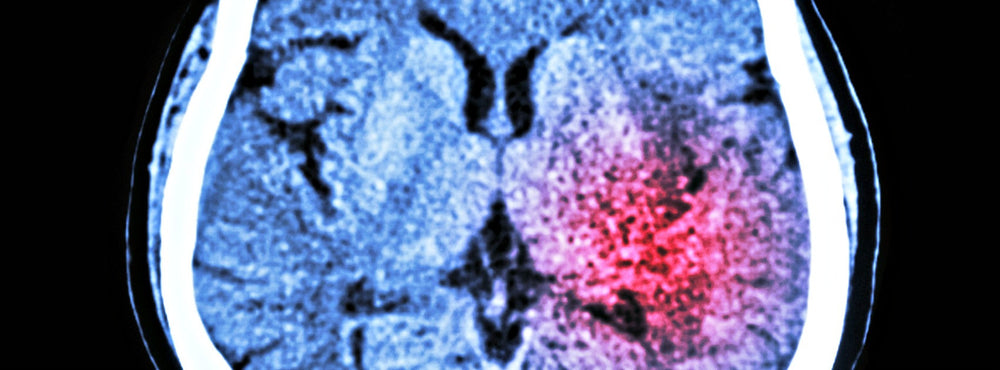

The Scary Reality of Strokes

Nearly 800,000 people in the U.S. have a stroke each year, making it the 5th leading cause of death in the country. Perhaps more alarming, stroke is the leading cause of long-term disability.